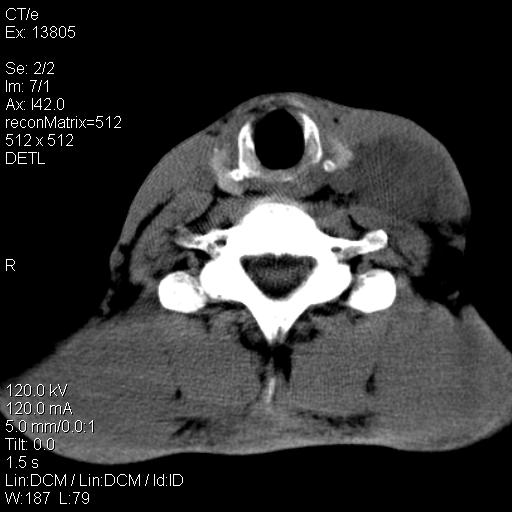

上腹部疼痛一月,呕吐10天,发现左侧颈部包快10天 胸部cr片未见明显异常。

左侧胸锁乳突肌下方、颈血管旁低密度肿块影,肿块密度尚均匀,边缘大部分清楚,邻近组织稍受压移位。考虑颈部神经鞘瘤可能性大。

颈部及腹膜后淋巴瘤可能性大